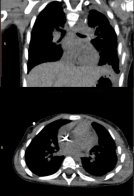

Батьки дівчинки регулярно проходили профілактичні огляди та не помічали жодних тривожних сигналів. Проте згодом у дитини раптово з’явилися біль у животі, висока температура та розлади травлення. Після УЗД і рентгену з’ясувалося, що ліва легеня майже не функціонувала через масивне утворення в грудній клітці.

“На рентгенівському знімку уся ліва легеня була “засвічена”. Фактично вона дихала лише однією легенею”, — згадують батьки дівчинки.

“У дитини виявили велике пухлинне утворення в лівій половині грудної клітки, яке повністю здавлювало ліву легеню та зміщувало життєво важливі органи. Ситуацію ускладнювала генералізована інфекція: стандартна агресивна хіміотерапія могла бути надзвичайно небезпечною. Проте через масивні розміри пухлини й компресію легені чекати було неможливо”, — розповіла онкологиня Неля Вовк.